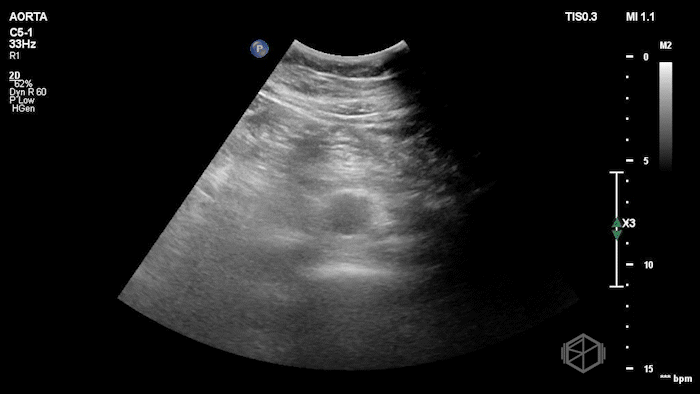

Dr. Singh grabbed the US and saw the following findings:

The POCUS shows a normal sized abdominal aorta, but with a visible flap moving internally. Given the patient has chest pain and near syncope, and extensive dissection was in the differential. Dr. Singh and Dr. Bernot expedited the patient to CTA which showed an extensive Type A aortic dissection. The patient went immediately to surgery and had a positive outcome.

Diagnosis: Type A Aortic Dissection